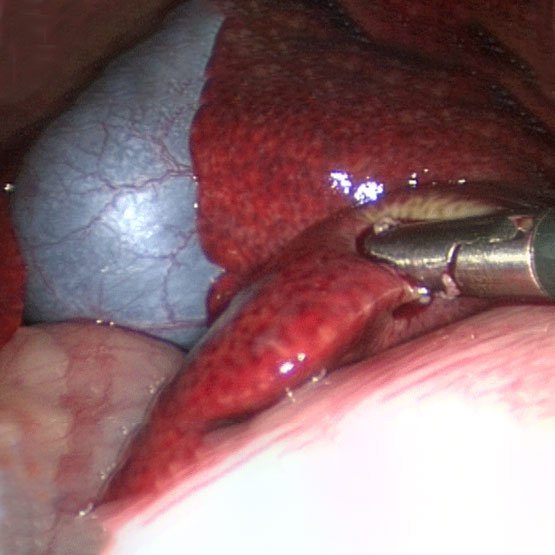

ByRL HYSTEROSCOPY INSTRUMENTS

Hysteroscopy is the clinical examination of the uterine cavity by endoscopy procedure with access through the cervix. It allows for the diagnosis of intrauterine pathology and serves as a method for surgical intervention (operative hysteroscopy). Its a minimal invasive procedure done by Gynaecologists.

Various instruments have been used to carry out Hysteroscopic procedure :- Diagnostic Hysteroscopy Sheath

- Operative Hysteroscopy Sheath

- Rat Toothed Alligator Hysteroscopic Grasper

- Hysteroscopic Scissors etc.

ByRL LAPAROSCOPIC GALL BLADDER EXTRACTOR

Gall Bladder extractor is used in General Surgery, Laparoscopic Surgery, Gastroenterology to grasp and remove Gall Bladder. Its also known as Claw Forcep.Product Features:

- Made up of Medical Grade Stainless Steel 304.

- Ergonomic handle and antislip surface handle for easy, firm and safe grip.

- Toothed jaws to hold, grasp and extract gall bladder firmly.

- Reusable/ autoclavable spring loaded Metal Handle.

- Available in 10mm diameter with 33cm length.